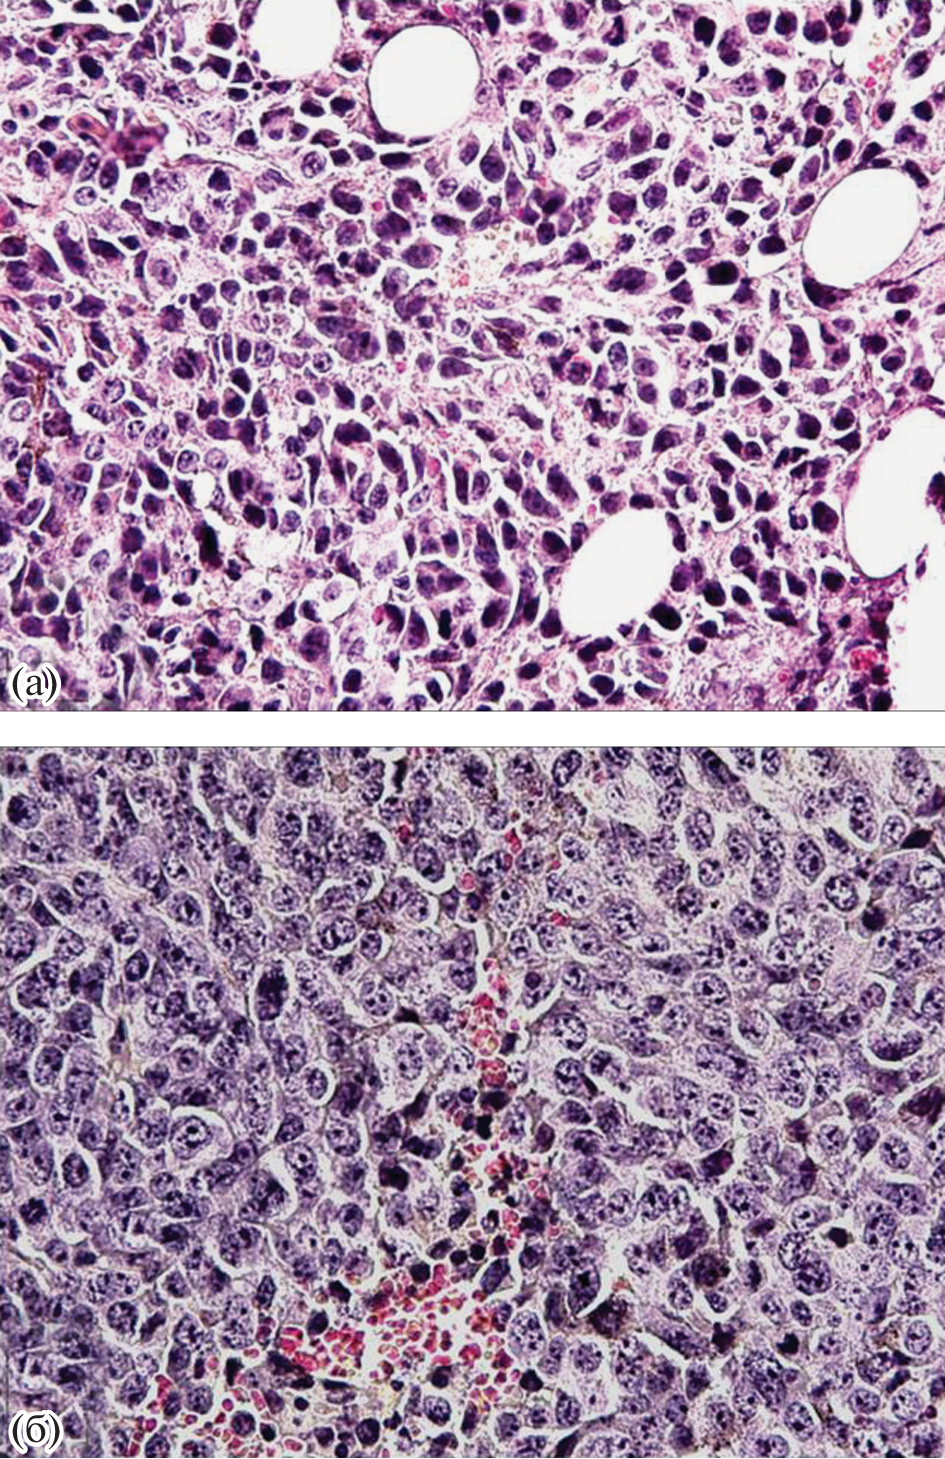

The aim of the study was to investigate the growth and development of B16 melanoma in mature male C57Black/6 mice with a post-traumatic stress disorder (PTSD) model. Behavioral, immunohistochemical, morphometric methods, enzyme immunoassay were used. A forced decrease in the level of corticosterone, which is characteristic for PTSD, was established, followed by an intensification of the production of increased concentrations of pro-inflammatory interleukins by the cells of the immune system and, at the same time, a decrease in the secretion of anti-inflammatory cytokines. Priority data were obtained: the neurohumoral imbalance that develops in PTSD is a limiting factor to the growth of B16 melanoma, at least at the initial stages of the oncological process.